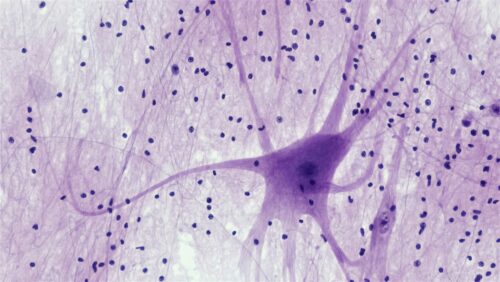

ALS/FTD are degenerative nervous system diseases, meaning they attack the nervous system progressively. ALS destroys the motor neurons that control muscles, leading to weakness, paralysis, and eventually fatal respiratory failure. FTD erodes neurons in brain regions governing personality and behavior, causing profound changes in a person’s character and ability to communicate. As the disease progresses, patients have a lower quality of life as they struggle with everyday tasks and simple movements.